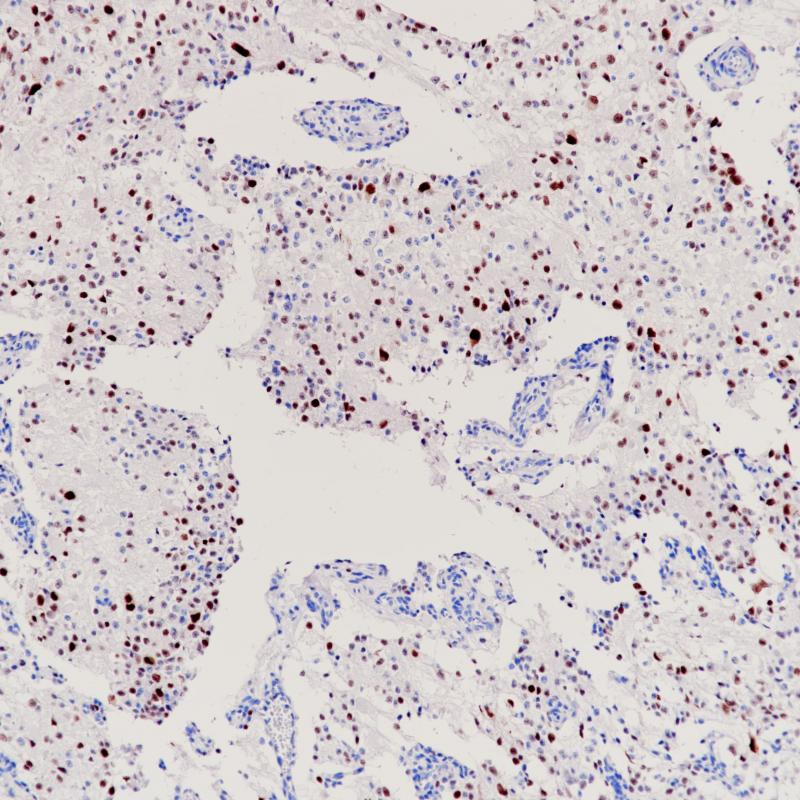

Estrogen Receptor α

BP6139